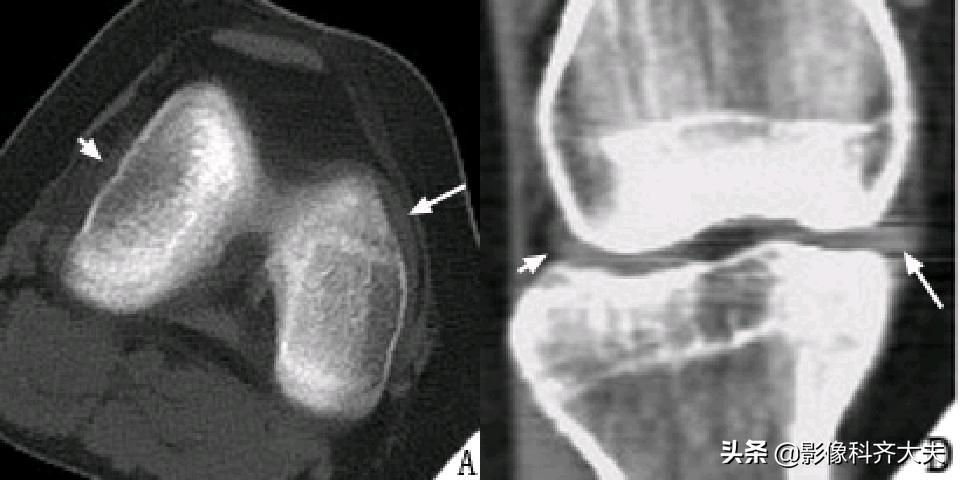

正常半月板CT扫描及重建图像